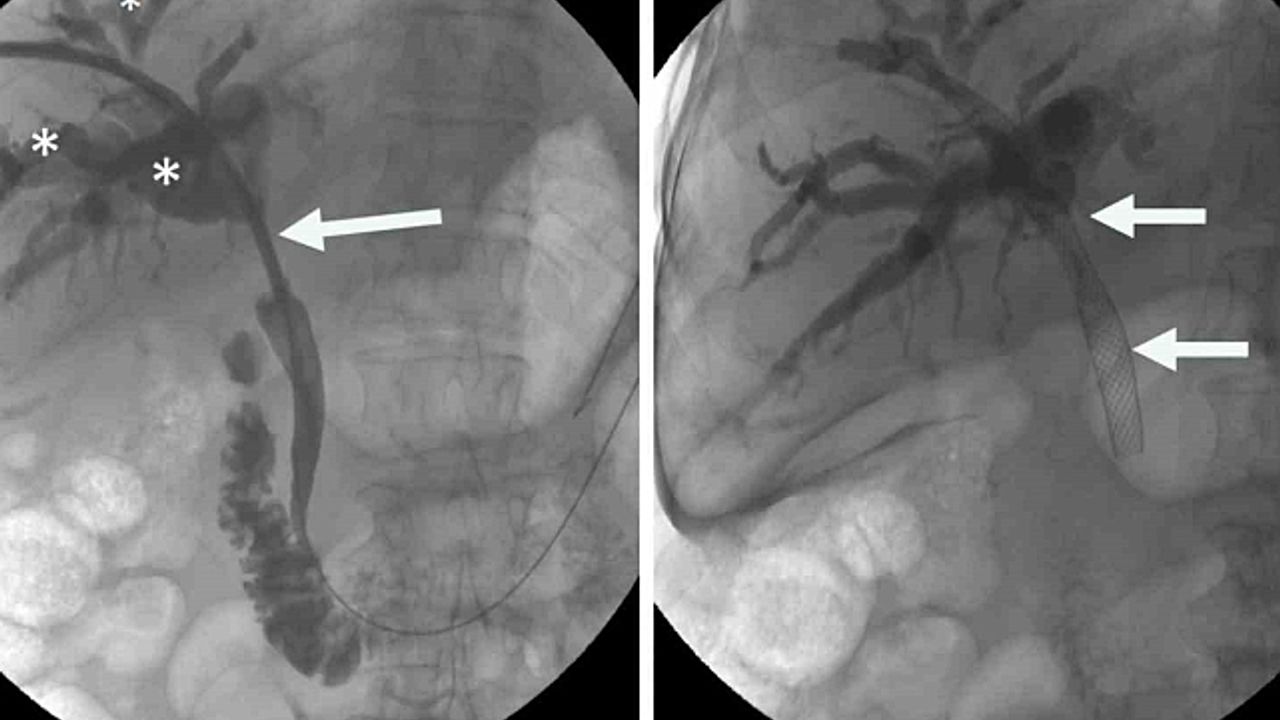

Prof. Dr. Ahmet Memiş''in önderliğinde uygulanan bu yenilikçi yöntem, endoskopik teknikleri ve iğne ile giriş yöntemlerini tek bir operasyonda birleştiriyor. Bu sayede, daha önce tedavisi çok zorlu kabul edilen karmaşık safra yolu problemleri artık daha etkili ve minimal invaziv bir şekilde tedavi edilebiliyor. Hibrit yaklaşımların en önemli avantajlarından biri, hastaların bedenine minimum düzeyde zarar vermesidir. Büyük cerrahi kesilerin yerine, endoskopik, gastro ve girişimsel radyoloji yöntemler kullanılarak, iğne deliği kadar küçük girişimlerle operasyonlar gerçekleştiriliyor. Bu da hastaların ameliyat sonrası ağrılarını azaltıyor, enfeksiyon riskini düşürüyor ve hastanede kalış sürelerini kısaltıyor.

Prof. Dr. Ahmet Memiş, "Hibrit yaklaşım, sadece tedavi değil, aynı zamanda tanı sürecinde de önemli avantajlar sunuyor. Hekim, hastanın vücuduna dokunmadan, radyolojik görüntüleme teknikleriyle hastalıklar daha hızlı ve doğru bir şekilde tespit ediliyor. Bu da tedavi sürecinin daha etkin bir şekilde planlanmasına imkan sağlıyor. Farklı disiplinlerden uzman hekimlerin bir araya gelerek oluşturduğu sinerji, karmaşık safra yolu sorunlarında başarı oranını önemli ölçüde artırıyor. Bu sayede, hastalar daha hızlı iyileşme göstererek günlük yaşamlarına daha kısa sürede dönebiliyor. Geleneksel cerrahi yöntemlerde uzun iyileşme süreleri ve yoğun ağrılar yaşanırken, minimal invaziv yaklaşımlar sayesinde bu sorunlar ortadan kalkıyor. Hastalar, operasyon sonrası çok daha kısa sürede taburcu oluyor ve gündelik aktivitelerine hızla dönebiliyorlar. Bu da hem hasta konforunu artırıyor hem de sağlık sisteminin üzerindeki yükü hafifletiyor" dedi.